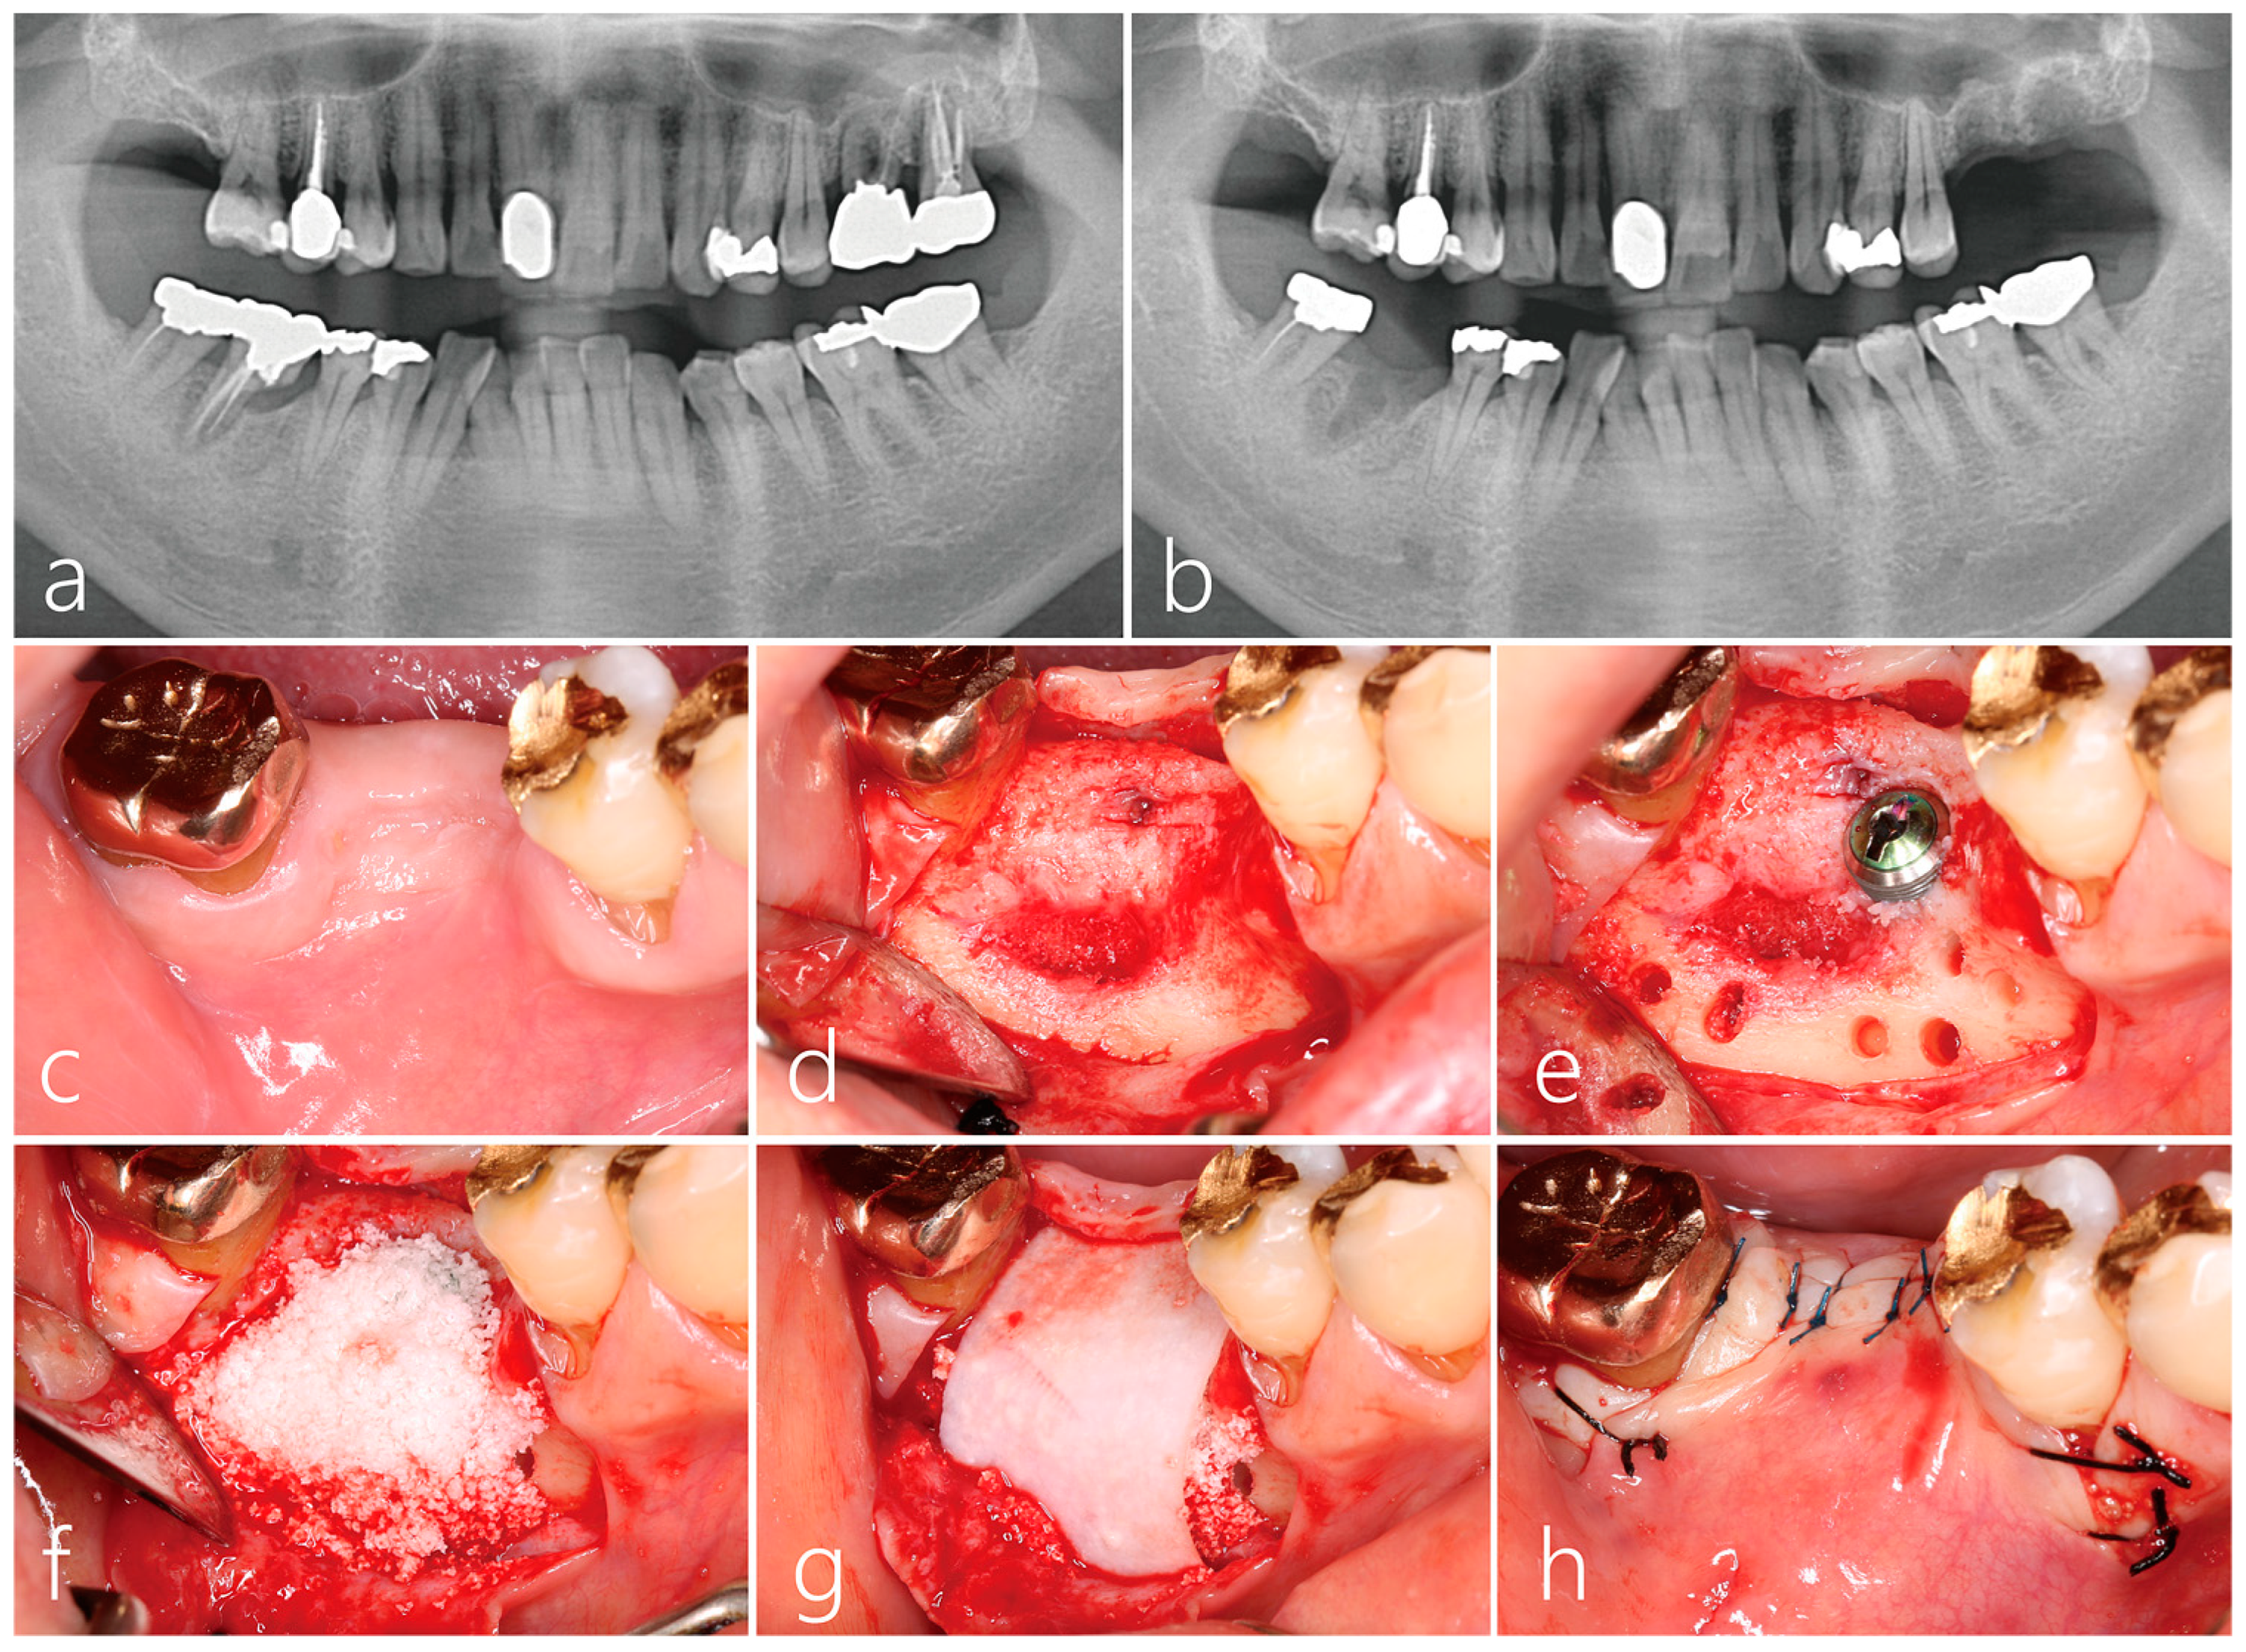

2.1. Implant Placement and Lateral Bone Augmentation

2.2. Uncovering Procedure